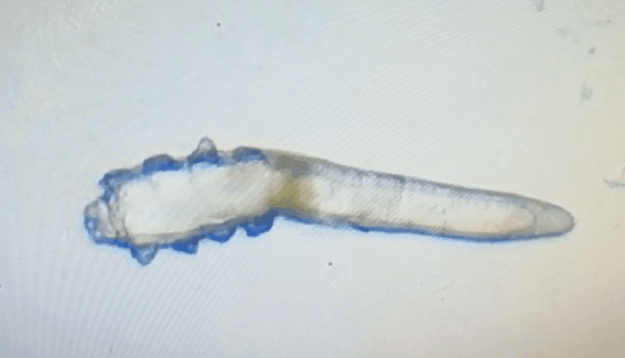

這就不得不提到眼科醫(yī)生經(jīng)常使用的螨蟲(chóng)檢測(cè)工具——螨蟲(chóng)鏡檢。它通過(guò)顯微利器,無(wú)死角全方位掃描你的睫毛,讓螨蟲(chóng)無(wú)處遁形。

林女士是一家公司的白領(lǐng),常常需要濃妝出席各種會(huì)議,然而光鮮亮麗的背后,林女士的眼睛正遭受著和陳先生同樣的癥狀。在螨蟲(chóng)鏡檢中,當(dāng)看到自己的睫毛上爬滿了十幾只透明的生物-螨蟲(chóng),林女士嚇了一跳。幸而,經(jīng)過(guò)廈門眼科中心干眼中心的治療,林女士解決了多年的眼睛干癢問(wèn)題。